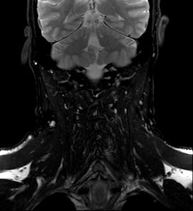

Prova diagnòstica no invasiva que consisteix en l'obtenció d'imatges d'alta definició anatòmica del coll mitjançant l'ús d'un camp electromagnètic i ones de ràdio (com un emissor i un receptor). No utilitza radiació ionitzant. Indicacions: sospita de tumor, infeccions, ganglis. - Angio-RM intracranial

Prova diagnòstica no invasiva que consisteix en l'obtenció d'imatges d'alta definició anatòmica de les artèries caròtides i vertrebrals a nivell de coll mitjançant l'ús d'un camp electromagnètic i ones de ràdio (com un emissor i un receptor). No utilitza radiació ionitzant. En la majoria dels casos és necessari l'us de contrast paramagnètic (Gadolino). Permet un estudi angiogràfic no invasiu gràcies a la injecció de Gadolino amb una reconstrucció posterior en 2D i 3D gràcies a estacions de treball especialitzades. Indicacions: problemes circulatoris cerebrals, síncope. - RM espectroscòpia cerebral